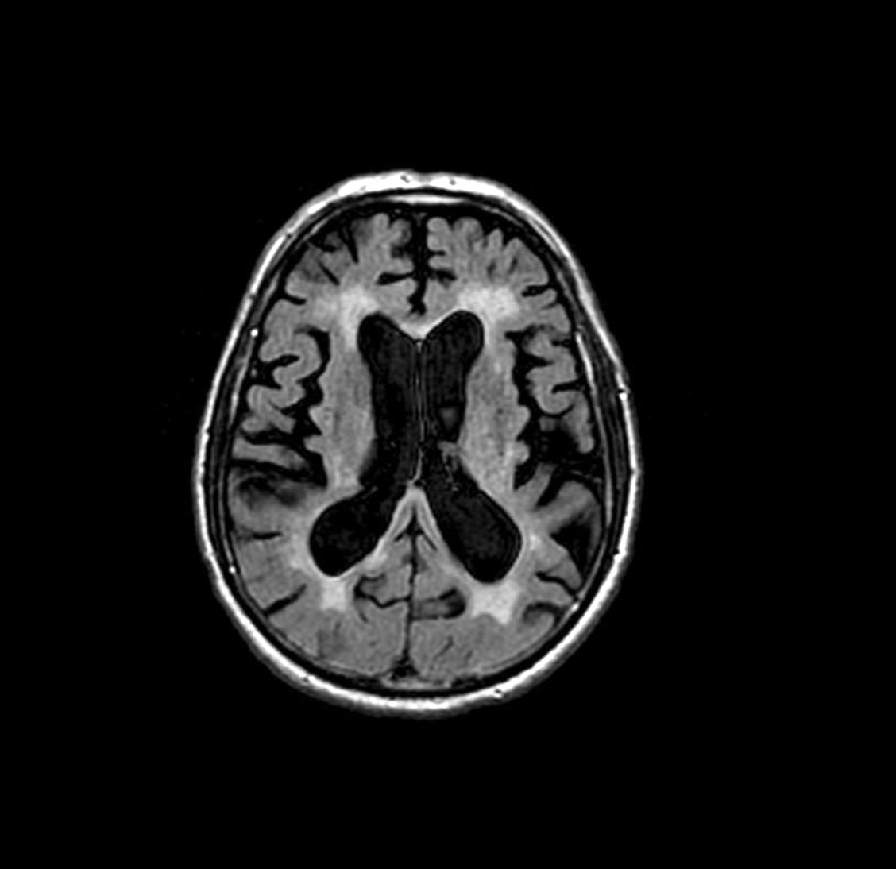

Autor: Adéla Bubeníková Zhoršená chůze, nejistota, zhoršení paměti, zpomalení vykonávání běžných aktivit a potíže s udržením moči. Ve vyšším věku bývá podobná kombinace příznaků často přičítána prostému stárnutí nebo začínající demenci. Jenže ne vždy musí jít o nevratný proces. Existuje onemocnění, o kterém se mimo odborné kruhy mluví jen zřídka, a přitom může stát za nápadnou...Read More